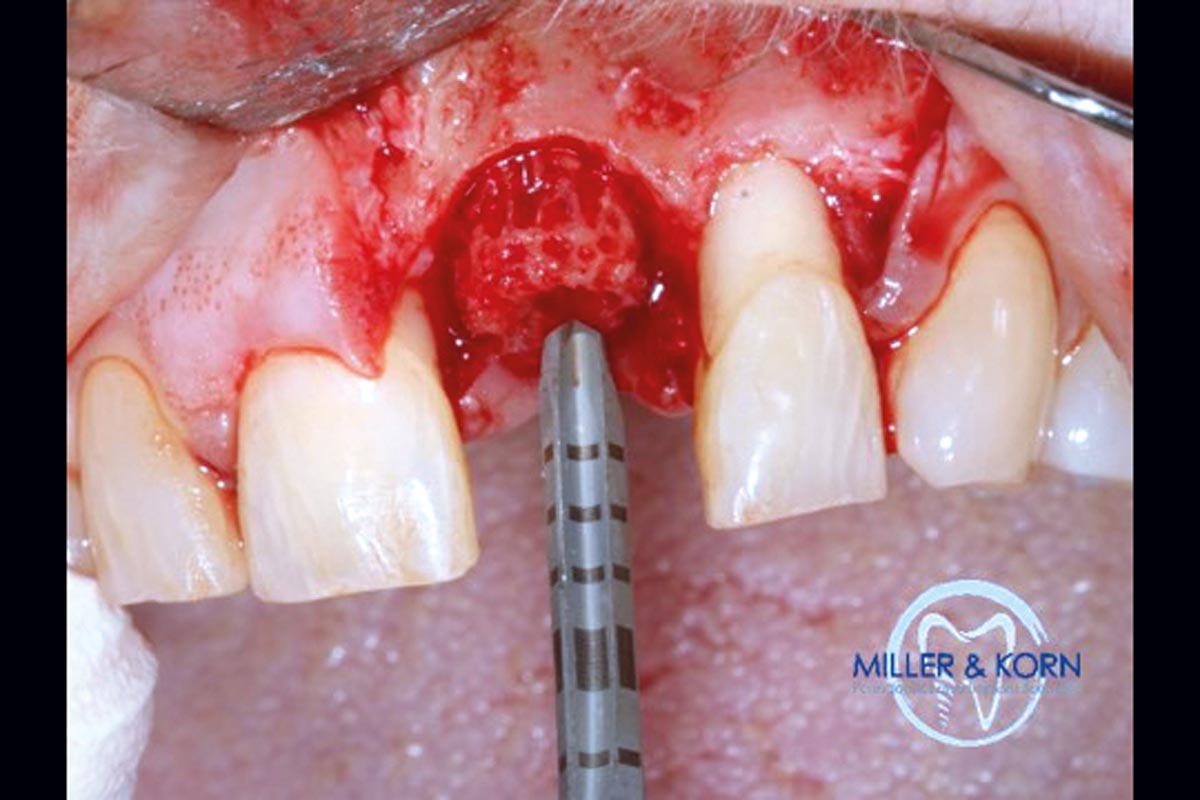

04/39 - Preparation of a full thickness flap and careful debridementImmediate implant placement and correction of horizontal and vertical bone loss using an allograft bone ring, cerabone® and Jason® membrane - Drs. Miller and Korn